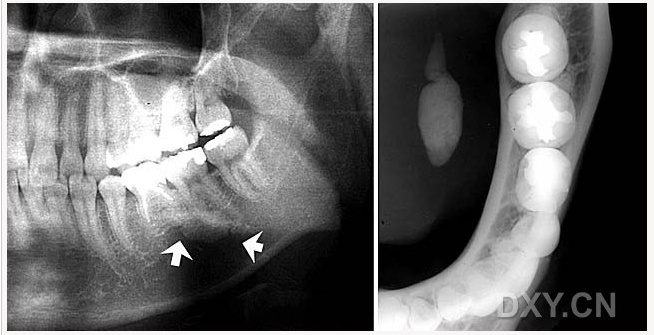

成釉細胞瘤

涎石病